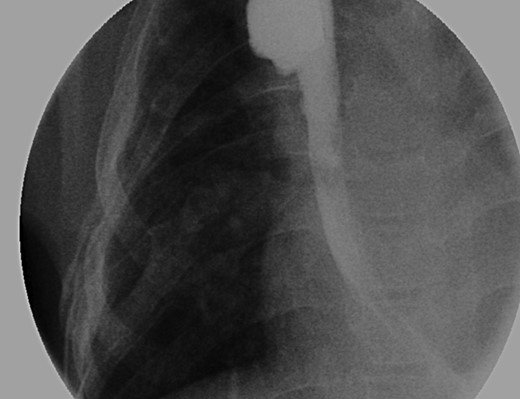

Daily tightening of her traction sutures was performed until the distal esophageal segment reached the chest wall (Fig. 2). The cervical esophagostomy was also sequentially lengthened and eventually internalized. Three traction suture revisions and two proximal esophageal lengthening operations were performed before esophageal continuity was re-established (46 days). Two subsequent anastomotic leaks occurred; 1 anastomotic leak was repaired surgically, whereas one subsequent leak was managed nonoperatively with a chest tube. Five dilations and, one, 13-day retrievable stent placement were needed for anastomotic narrowing. A comparative postoperative esophagram and intraoperative esophagram illustrated neither a stricture nor an anastomotic leak (Fig. 3). Total hospitalization was 112 days.

Fluoroscopic examination illustrating incremental ‘growth’ of the distal (lower) esophageal segment while the patient was undergoing external traction (Foker Stage 1). The contrast was injected through her existing gastrostomy tube. The metal dot refers to her esophagostomy; thus, can measure the distance between the ends of her esophageal segments.